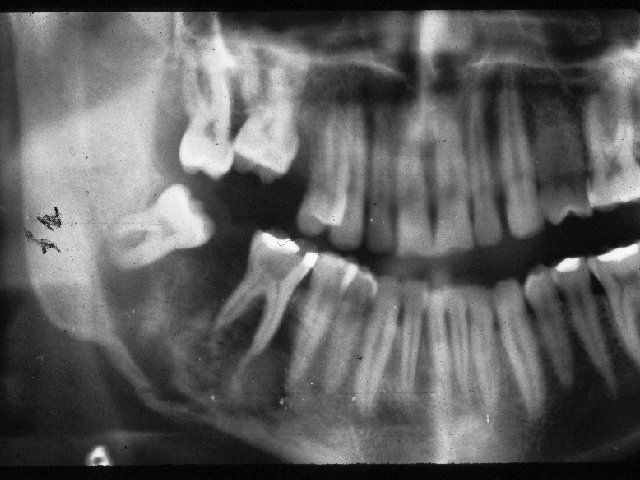

Osteogenic sarcoma (mixed) .

• Mixed – patches of neoplastic bone formed within a poorly defined radiolucency with variable internal radiopacity.